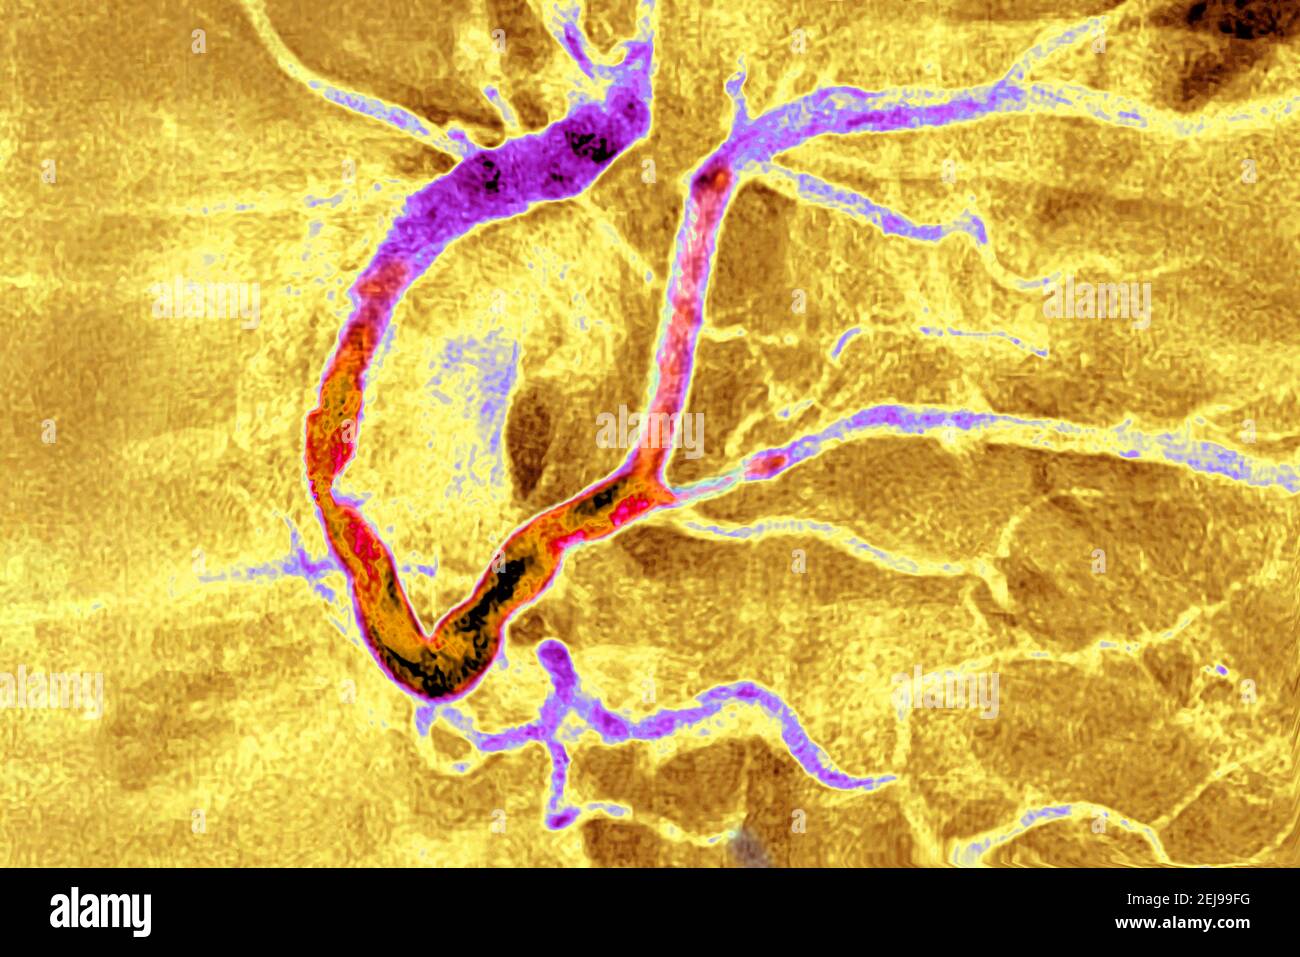

Myocardial infarction with a significant thrombus Stock Photohttps://www.alamy.com/image-license-details/?v=1https://www.alamy.com/myocardial-infarction-with-a-significant-thrombus-image407107332.html

Myocardial infarction with a significant thrombus Stock Photohttps://www.alamy.com/image-license-details/?v=1https://www.alamy.com/myocardial-infarction-with-a-significant-thrombus-image407107332.htmlRM2EJ99FG–Myocardial infarction with a significant thrombus